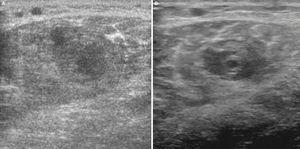

Utilizando el equipo E-A, en un corte longitudinal sobre el músculo gemelo externo a la altura del tercio superior (fig. 2A) se observa la referencia ósea que corresponde a la cortical del peroné, y en un plano superior no se aprecia discontinuidad focal de las fibras ni la presencia de un hematoma intramuscular, debido posiblemente al prolongado tiempo de evolución (1 mes). Por el contrario, con E-B se aprecia una zona hipoecoica en el vientre muscular del gemelo externo (fig. 2B), de aspecto irregular y lineal no visualizable con el E-A, lo cual facilita la confirmación ecográfica de la sospecha clínica.

Figura 2 A) Aspecto fibrilar normal en un corte longitudinal del músculo gastrocnemio externo sobre el peroné en una imagen de E-A. B) En un corte longitudinal con E-B se observa el área hipoecoica en el vientre del gemelo externo.